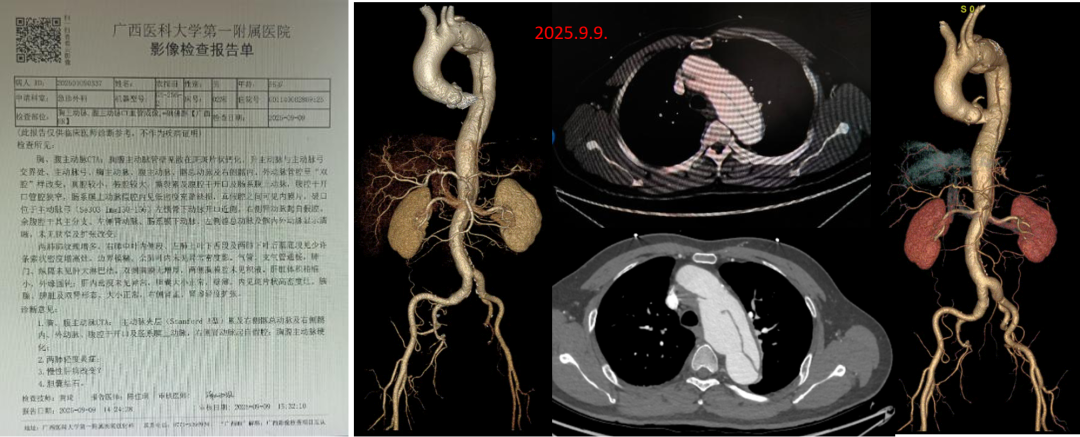

★ Case6:男,55岁, 胸痛4天入院。诊断:A型主动脉夹层

3D打印模型

分支前后体外预开窗

术毕造影

术后CTA

★ Case7:35岁, 主动脉夹层TEVAR术后( Castor 重建LSA)。4个月后出现新发破口(逆撕),累及左颈总动脉